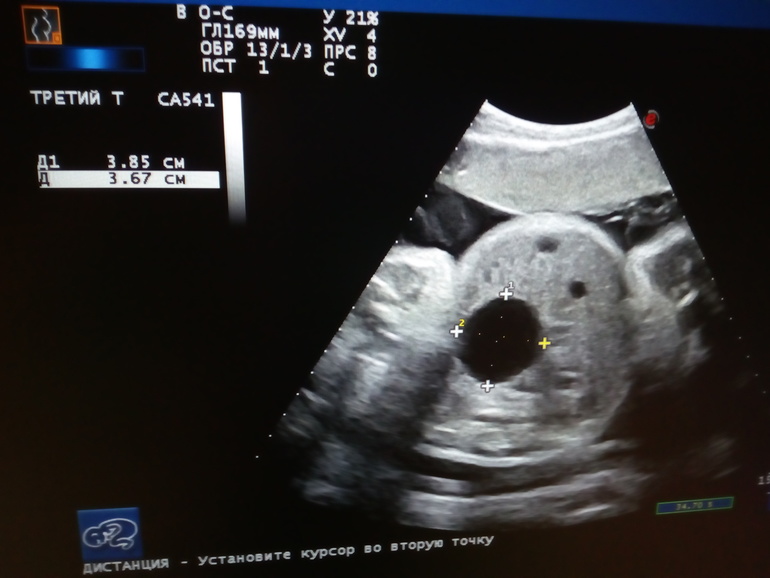

Вам совсем чуть-чуть осталось до встречи с малышом) а нам ещё 35 недель. На узи нашли образование 4 см. Подозрение на кисту яичника. Что чувствую не передать словами. Через неделю узи контроль. Может знаете что-нибудь об этом?

Надеюсь, что ошибка. Для меня моя девочка это всё. Три года не получалось забеременеть. Вот такую штуку нашли....